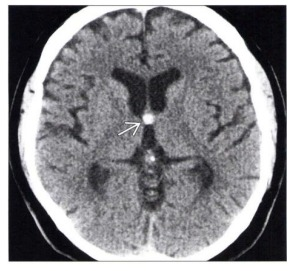

Tomografia do crânio sem contraste em corte axial ao nível do forame de Monro demonstra a imagem apontada pela seta na figura abaixo. O diagnóstico CORRETO é:

Enunciado 3505930-1